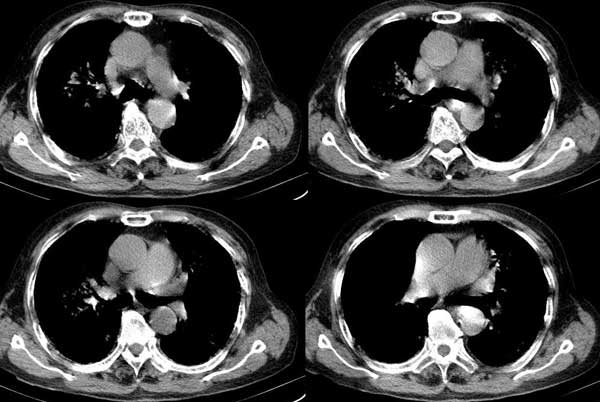

以下是引用dalianren在2006-7-20 21:23:00的发言:[br]我考虑是肺泡蛋白沉积症:典型表现为两肺内散在片状\"磨玻璃\"样混浊区呈地图样分布.

以下是引用lj0804在2006-7-21 12:57:00的发言:[br]支持[br]我考虑是肺泡蛋白沉积症:典型表现为两肺内散在片状\"磨玻璃\"样混浊去呈地图样分布.